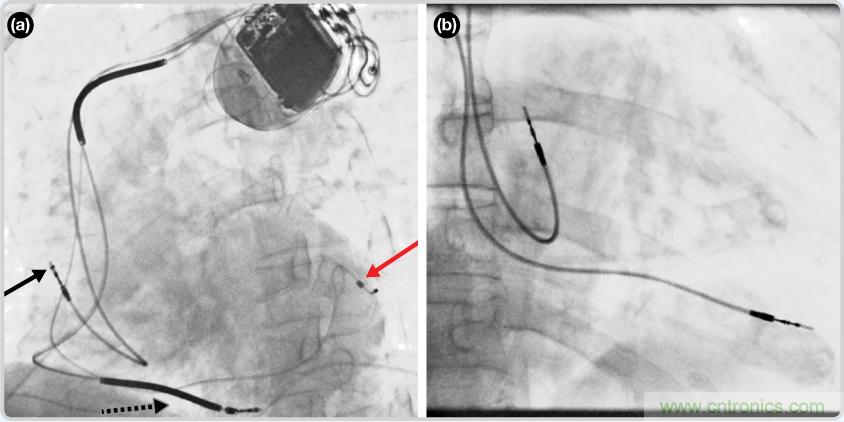

CRT器件在圖4(a)中的透視圖像中可以看見。醫(yī)師就是利用這種影像來放置導聯(lián)線的。對于非專業(yè)人士來說,這種影像是很難解讀的。可以看到心臟淡淡的輪廓——這是搏動中的心臟的靜態(tài)視圖。起搏器位于右心房上,心臟頂點指向右下方。在這個典型的導聯(lián)線放置實例中,黑色箭頭指向右心房導聯(lián)線。虛線黑色箭頭指向右心室導聯(lián)線。紅色箭頭標示的導聯(lián)線只能看到一部分,這是左心室導聯(lián)線(紅箭頭指向電極尖端)。圖4(b)展示的是雙腔起搏器的典型導聯(lián)線放置透視圖像。右心房導聯(lián)線指向上方,置于右心房中。右心室導聯(lián)線則位于右心室頂部。

圖4. 起搏器導聯(lián)線放置的透視圖像3 (a). 單腔起搏器;(b).雙腔起搏器